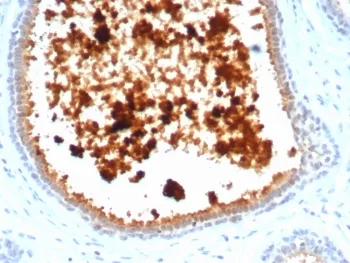

Mammaglobin, 10 kDa, is a cytoplasmic protein, a mammary-specific member of the uteroglobin family. It is related to a family of epithelial secretory proteins that includes prostatein and Clara cell protein. Mammaglobin occurs in about 80% of breast carcinomas. The extend is generally larger than that of GCDFP-15. Up to 15% of non-breast carcinomas (such as stomach, lung, colon, hepatobiliary, thyroid, ovarian, and urothelial carcinomas) have been reported positive, usually only focally. Mammaglobin is a sensitive and fairly specific marker for breast carcinoma.UniProt:

IHC-PFormat: